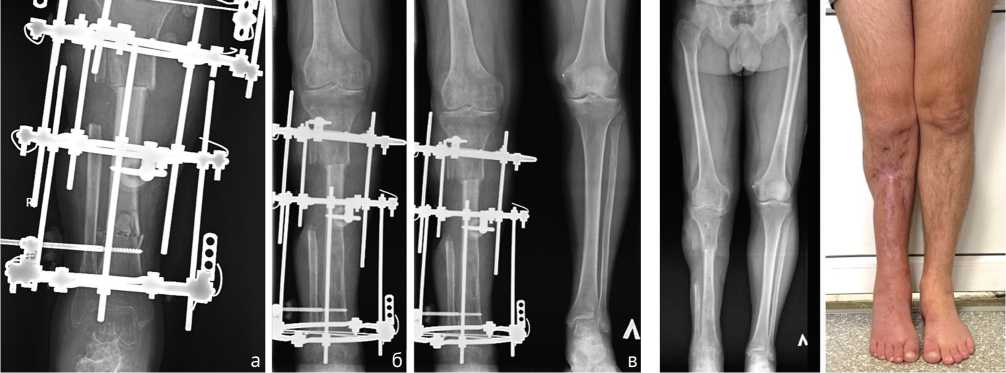

Через 126 дней после ранения (на 92-е сутки после ОУ) выявили признаки сращения отломков и выполнили остеотомию в нижней трети большеберцовой кости (рис. 9 и 10, а).

Удлинение проводили в течение 137 дней после укорочения (рис. 10, б) до 263-го дня после ранения (рис. 10, в). Сращение в зоне контакта отломков отметили на 192-й день после ОУ. В последующем проводили «воспитание регенерата» методом «аккордеона». Созревание регенерата отметили через 108 дней после прекращения удлинения. На 371-й день после ранения выполнили демонтаж АВФ. Продолжили реабилитацию в течение 60 суток (рис. 11).

Рис. 11. Телерентгенограмма и фото нижних конечностей пациента после окончания лечения

Рис. 10. Рентгенограммы: а — правой голени после остеотомии; б — правой голени в процессе удлинения большеберцовой кости; в — обеих голеней после окончания удлинения правой большеберцовой кости

Общий срок лечения составил 431 день, ИВФ — 29,7 сут./см. Остаточное укорочение 2 см. Анатомический результат по шкале ASAMI — хороший, функциональный — хороший.